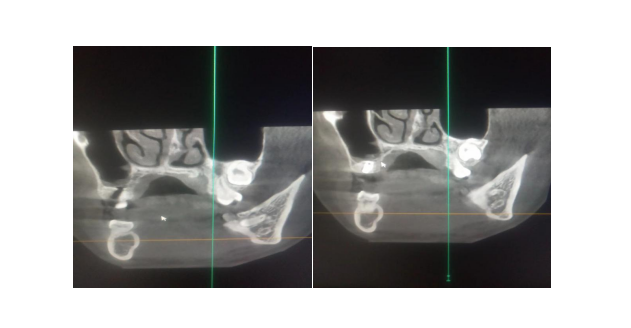

近日,我院口腔科成功开展了上颌窦内提升同期种植体植入术,常规阻滞麻醉及术区浸润麻醉,缺牙区牙槽嵴顶水平“一”字切口,切开粘骨膜翻瓣,暴露牙槽嵴顶,球钻平整牙槽嵴顶定位。用先锋钻钻入距上颌窦底1~2mm处,通过阻力评估种植区牙槽骨疏密情况,改用登腾上颌窦内提升工具盒逐级扩大至接近设计直径,保留颊舌侧骨板不少于1mm,在上颌窦窦底开窗,推起窦底粘膜向窦腔提升至合适深度,然后根据实际提升窦底到牙槽嵴顶的距离选择适宜长度的登腾种植体植入,关闭粘膜伤口。术后口服抗生素一周,漱口水含潄,一周拆线,定期拍片检查。

上颌后牙缺失患者往往由于缺牙引起牙槽骨萎缩、上颌窦气化而造成上颌窦窦底相应部位牙槽嵴高度降低,骨量不足,种植体易穿入上颌窦引起感染或种植区长度不足引起初期固位力下降不稳而导致种植失败,是口腔种植修复的难题。使用闭合式上颌窦内提升术(不植骨)同期植入术,大大提高了上颌后牙种植的成功率。